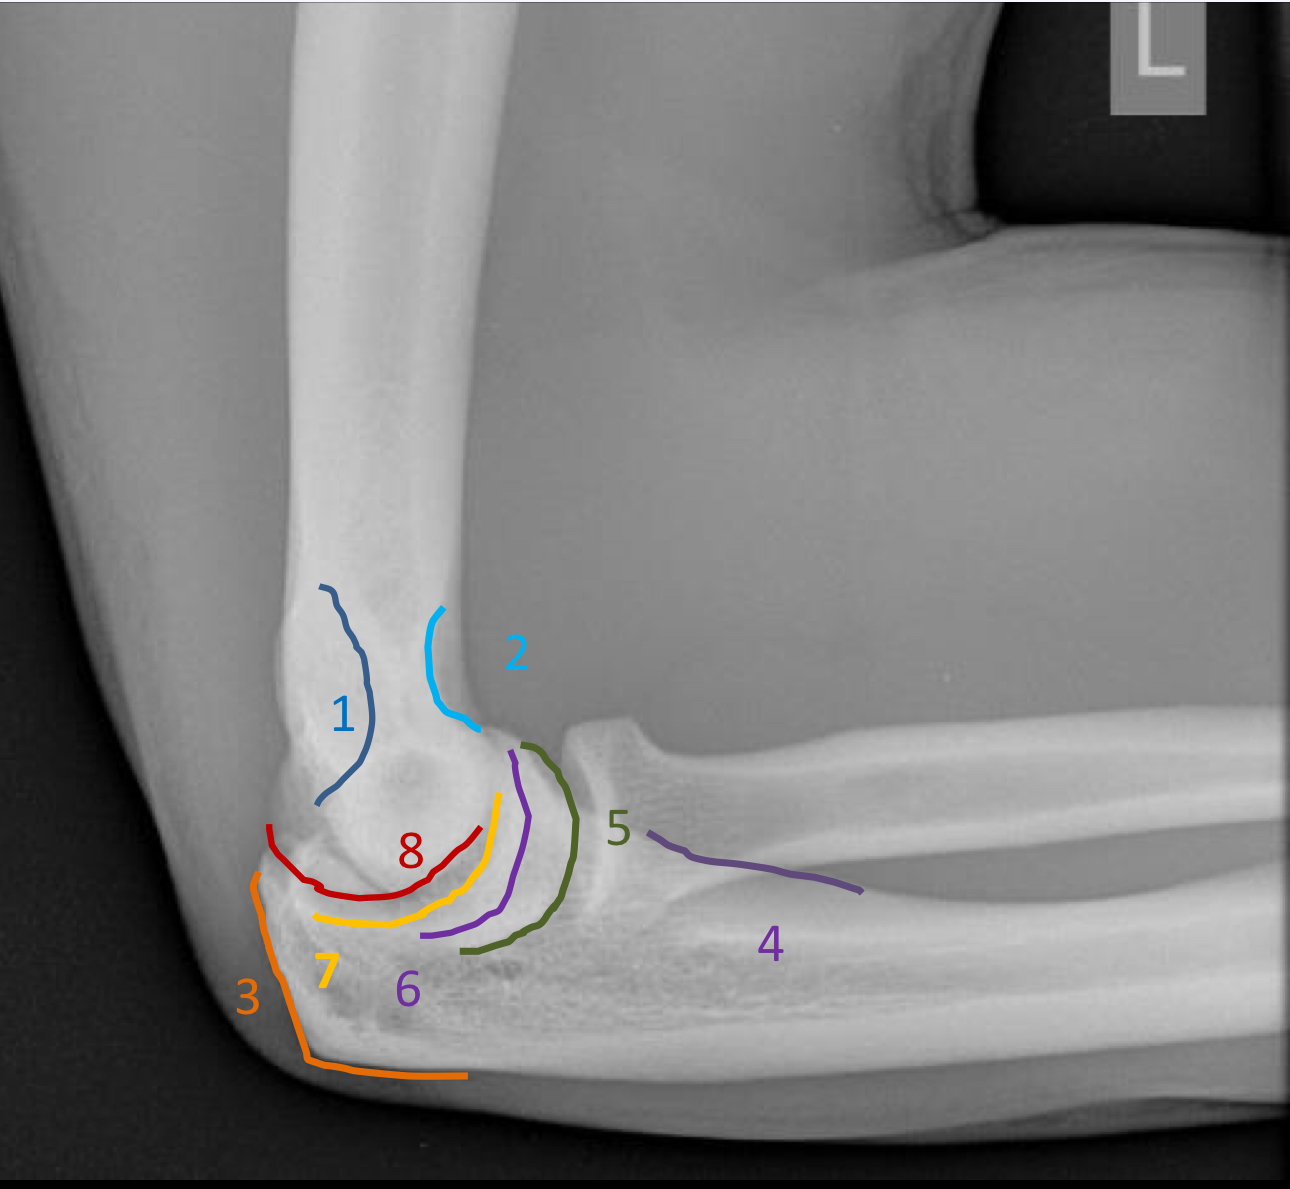

1?

medial epicondyle

2?

medial supracondylar ridge

3?

lateral epicondyle

4?

lateral supracondylar ridge

5?

radial head

6?

capitellum

7?

trochlea

8?

anterior trochlear notch including coronoid process